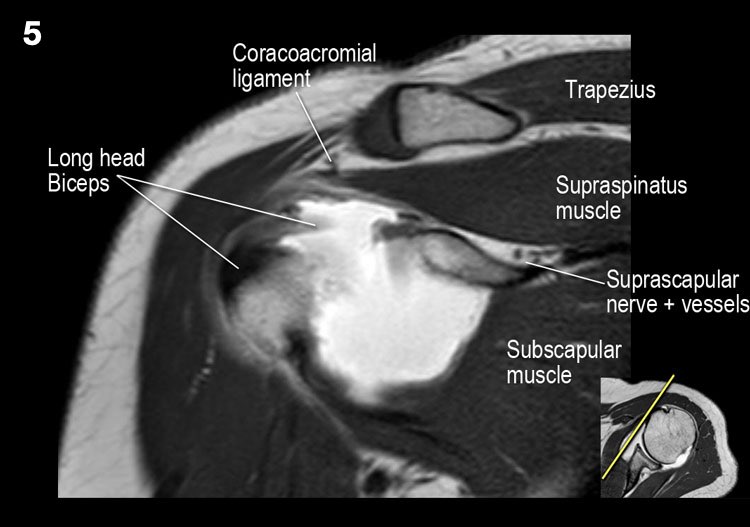

Giải phẫu mặt cắt vành và danh sách kiểm tra

- Lưu ý thần kinh và mạch máu trên vai.

- Đánh giá phức hợp sụn viền-gân cơ nhị đầu phần trên và tìm kiếm túi cùng dưới sụn viền hoặc rách SLAP.

- Tìm kiếm tràn dịch quá mức trong túi hoạt dịch dưới mỏm cùng vai và rách gân cơ trên gai.

- Tìm kiếm rách kiểu “rim-rent” của gân cơ trên gai tại chỗ bám của các thớ sợi trước.